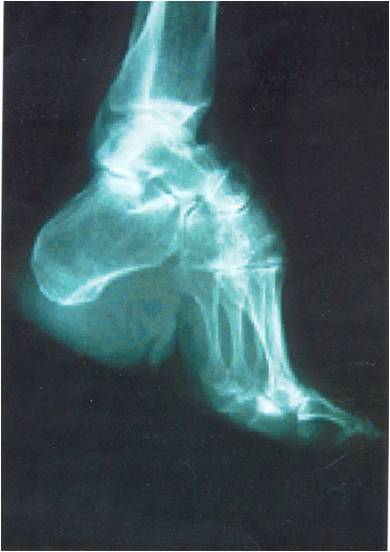

三寸金莲,或称为缠足,指的是中国女性为追求尖小的足形,不惜在女孩年幼时,以缠脚布紧缠双足,使足骨变形以限制脚板生长的风俗。当时谈论婚嫁时,信奉看人先看脚,因此在明清时代,只要力有所及,再贫穷的家庭也会设法让女儿缠足,以期能让女儿拥有较好的归宿。

弓、弯、纤、小是缠足既明确又模糊的指标,因为这四个要素可能组合成各种不同形状和尺寸的模板,这暗示了当时的情色想像可能带有时代及地域上的区别。例如宋代和元代出土的遗物显示,当时流行脚尖上翘的平底纤足;明清时代男性文人琅琅上口的莲瓣或玉笋,却将脚背隆起,创造出小而尖的视觉效果。弓、弯、纤、小的各种组合不但是情色想像的来源,也是创造时尚的指标。